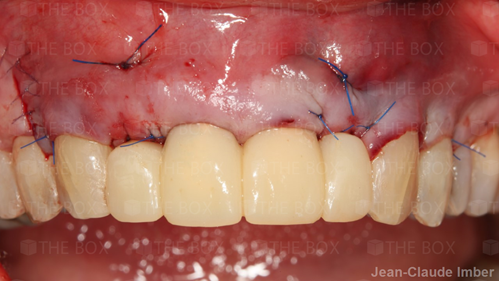

A new case was made public by Jean-Claude Imber check it out here.